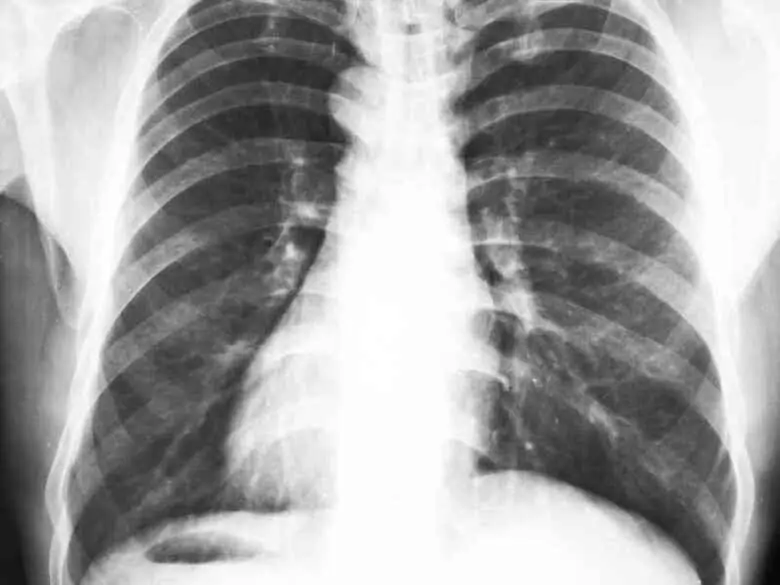

RTG klatki piersiowej